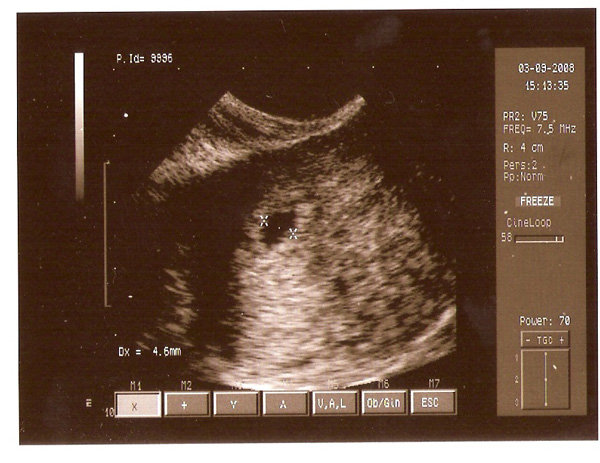

Még 10 nap és megyek a 2. uv-re!

Remélem lesz már szívhang.